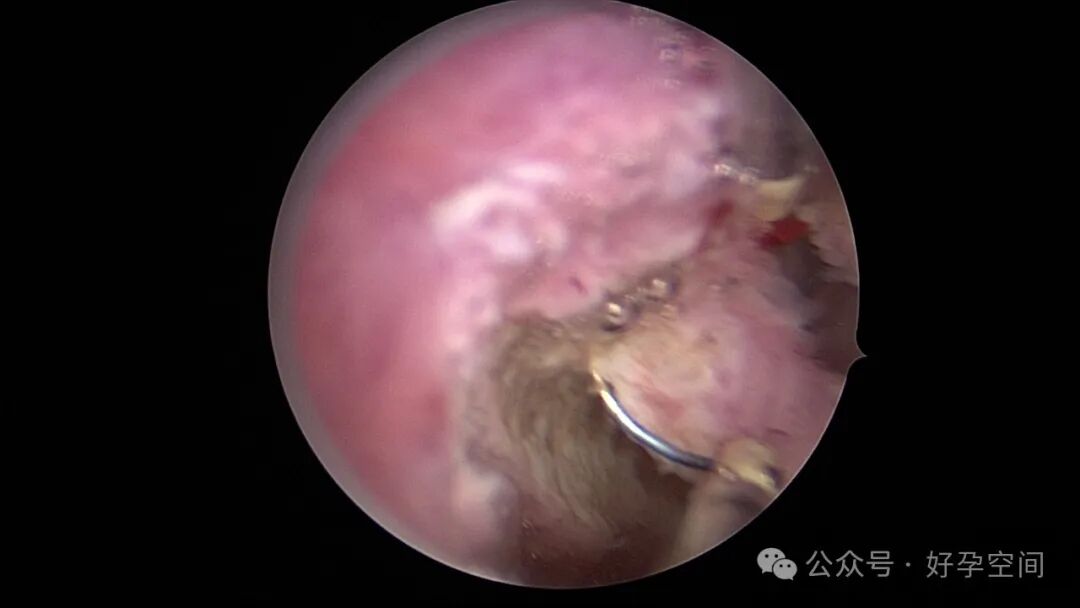

患者24岁,G6P3,顺产1次,双胎剖宫产1次。本次停经53天,计划外妊娠,行宫腔镜取胚及安环术。摘除胚胎后见宫腔右侧壁胚胎附着部位包块,约1.0cm*1.0cm*0.8cm,宫腔镜切除包块送病检,放置γ环一个,环两臂卷曲于右侧宫角,宫腔镜钩住环尾部下拉,上推节育环右臂,将环调整到正常位置。术后病检结果为“宫腔胎盘附着部位超常反应”。